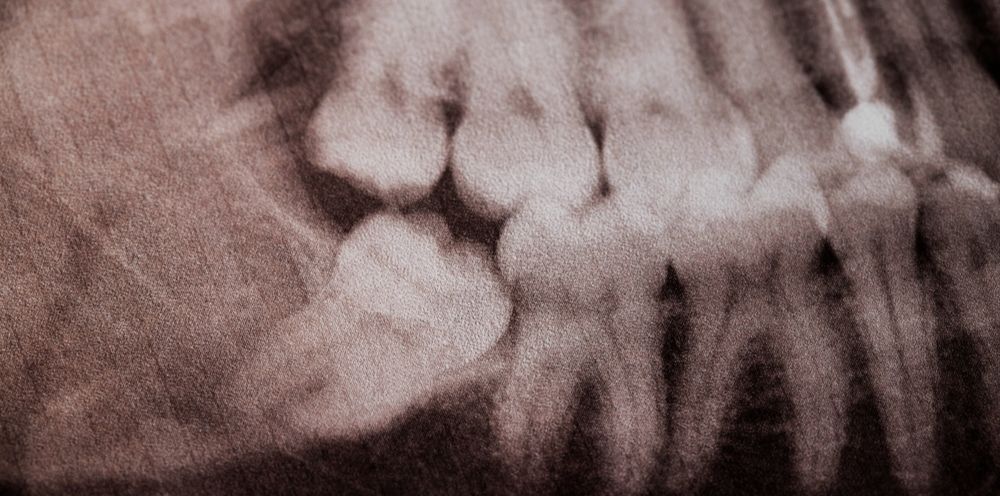

Dokter gigi biasanya akan melakukan pemeriksaan lebih lanjut, seperti foto rontgen gigi, untuk melihat kondisi gigi bungsu secara lebih jelas. Penanganan yang tepat dan cepat bisa mencegah timbulnya komplikasi, seperti abses dan infeksi, yang semakin meluas.